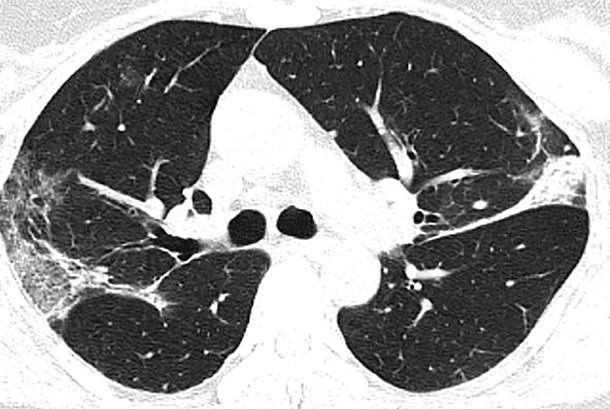

Corona Sorunlu Akciger Filmi

Corona Virusunun Akcigerlere Zarari Gosteren Tomografi Filmi